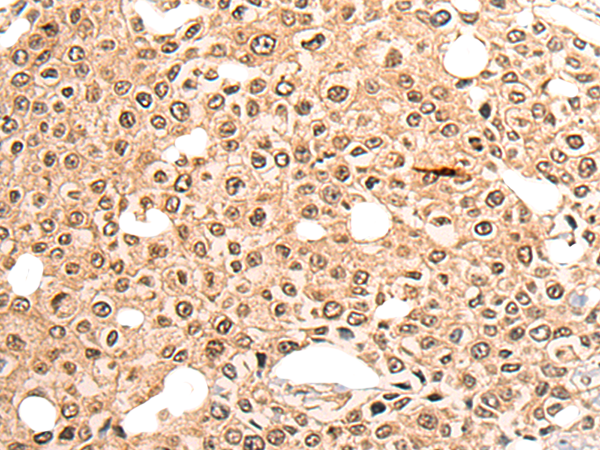

IHC positive control: |

Human colorectal cancer and human lung cancer |

IHC Recommend dilution: |

20-100 |